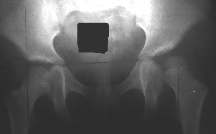

A four year old female with Down's Syndrome presented to the emergency room with the left hip flexed, adducted and internally rotated. This occurred after a fall from a tricycle. The mother previously reported clicking in the left hip which had been present since age 2.

An xray is obtained which shows a dislocated hip. This will require a general anesthesia for a reduction to be obtained.